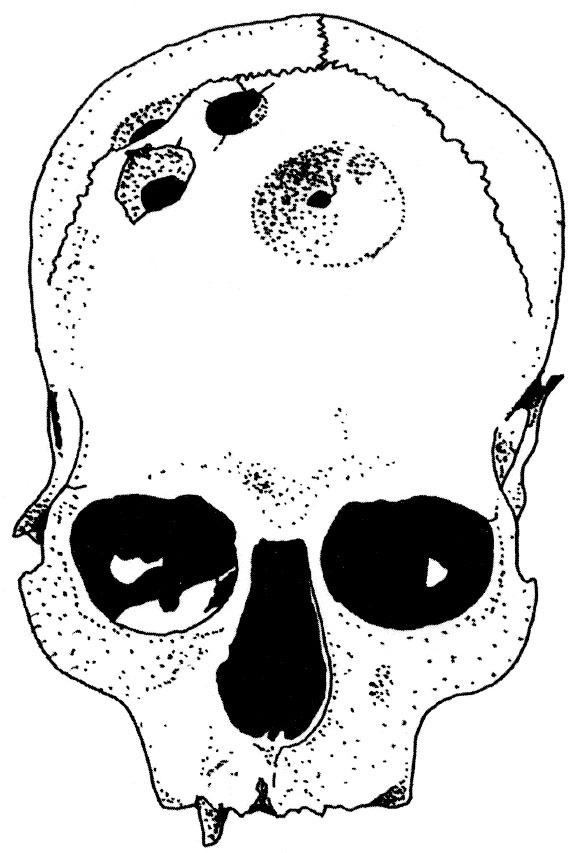

На наш взгляд, самое точное, простое и всеобъемлющее определение трепанаций – удаление участка кости из черепа (Ф. Лисовски (Рис. 10)) или «полное или частичное удаление фрагмента кости из свода черепа» (В. Я. Дэрумс). Такого расширительного понимания трепанаций, восходящего к трактовке П. Брока, мы и будем в дальнейшем придерживаться.

Рис. 10. Различные техники трепанирования, применявшиеся в древнем мире (по Ф. Лисовски). а – скобление, б – прорезание, в – сверление небольших отверстий и прорезание «мостика» между ними, г – иссечение фрагментов прямоугольной формы.

С этим связаны определенные трудности в работе экспертов. Не имея в руках истории болезни, не так просто отличить прижизненные операции, вскоре после которых пациент скончался, от посмертных вскрытий (Рис. 11). Разработана подробная дифференциальная диагностика, предусматривающая, что «дополнительные» отверстия в голове человека могут появиться под воздействием травм, болезней или даже иметься от рождения.